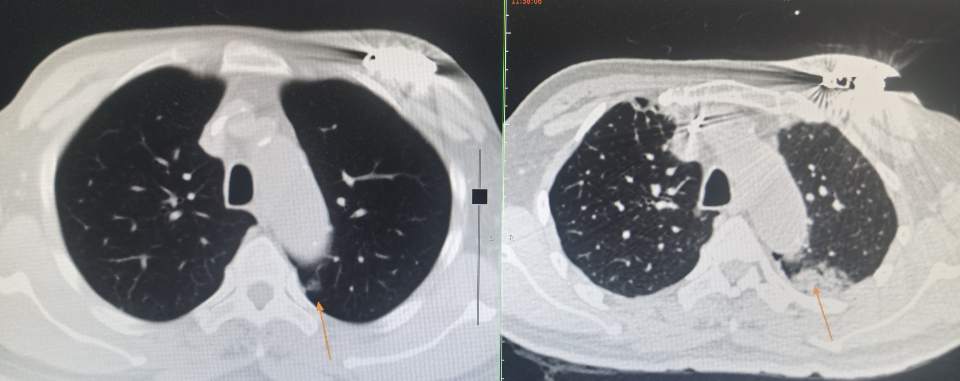

手术前李医生对肺结节进行了一个三维重建,明确了肺结节跟血管和胸膜之间的关系,然后对他的整个手术的操作路径进行了周密和详细的规划和预测,在手术的当天也把林老师的整个呼吸和血压心率控制在比较平稳的范围,并且对他的身体状态进行了合适的调整,让林老师在一个比较舒适和平静的状态接受手术,最大限度的减少其他因素对手术的影响。

正如手术前的预测,术中消融针一次到位,完美避开胸膜和主动脉直接到达结节的位置,真可谓一针扎进结节里!

而且经过深思熟虑,李医生特意给他选择了冷冻消融治疗,对血管和胸膜的刺激最少,而且可以最大范围的包裹住肺结节,对肺结节里面的病灶进行完美的杀灭。

手术后的CT也完美的验证了术前的预测,冷冻消融完美的包裹住了肺结节,同时对胸膜和肺动脉主动脉没有任何的影响,随着时间的推移,冷冻形成的病灶会逐渐吸收并消失。肺结节消融,冷冻消融,这是一次完美的手术,林老师非常满意的收获了不手术治疗肺结节带来的快乐!